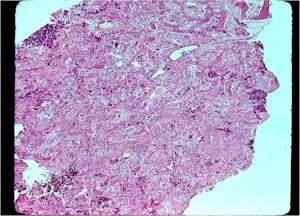

Microscopic Pathology

- Interlacing network of bone trabeculae in a loose fibrovascular stroma

- Prominent vessels

- Osteoblasts are plump, active, scattered mitotic figures

- Osteoblasts line up around periphery of trabeculae (Osteoblastic Rimming)

- Soft tissue component usually surrounded by shell of reactive bone or periosteum (Egg Shell Rim of Calcification)

- No cartilage production (as opposed to osteosarcomas that may contain areas of cartilage)